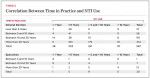

The grinding and clenching of teeth, commonly termed bruxism, can occur during sleep as well as during wakefulness.1 These parafunctional episodes are categorized as either idiopathic or iatrogenic and may be the result of a variety of causes, including medications, medical disorders (including Parkinson’s disease, tardive dyskinesia, myoclonus, tic, depression, and anxiety), and natural orofacial events (such as swallowing, somniloquy, and sighing).1 Awake bruxism is reported to be present in 20% of the adult population. (Table 1).2 The prevalence of sleep bruxism peaks in the 25–44 year age range and declines with aging. The incidence is 5.5% among 15–18 year olds, 9.2% among 19–24 year olds, 10.5% among 25–44 year olds, and 8.8% among 45–64 year olds.3

Of the available 5,807 surveys, a total of 587 (10.11%) were completed by participants. A survey was considered completed if participants reached the last question and exited the survey. Providing answers to all 37 questions was not an inclusion criteria for considering the questionnaire completed. Providers placed an average of 160 (SEM ±13.8; 95% CI 133,187; median of 60) devices in their practices since starting use of the NTI-tss appliance. Time in practice of responders and years of experience with the device are presented in Table 2. Overall, 65.8% of responders had more than 20 years of clinical practice experience. The NTI-tss was used mostly by general dentists, with 58% of responders using the device for more than 5 years.